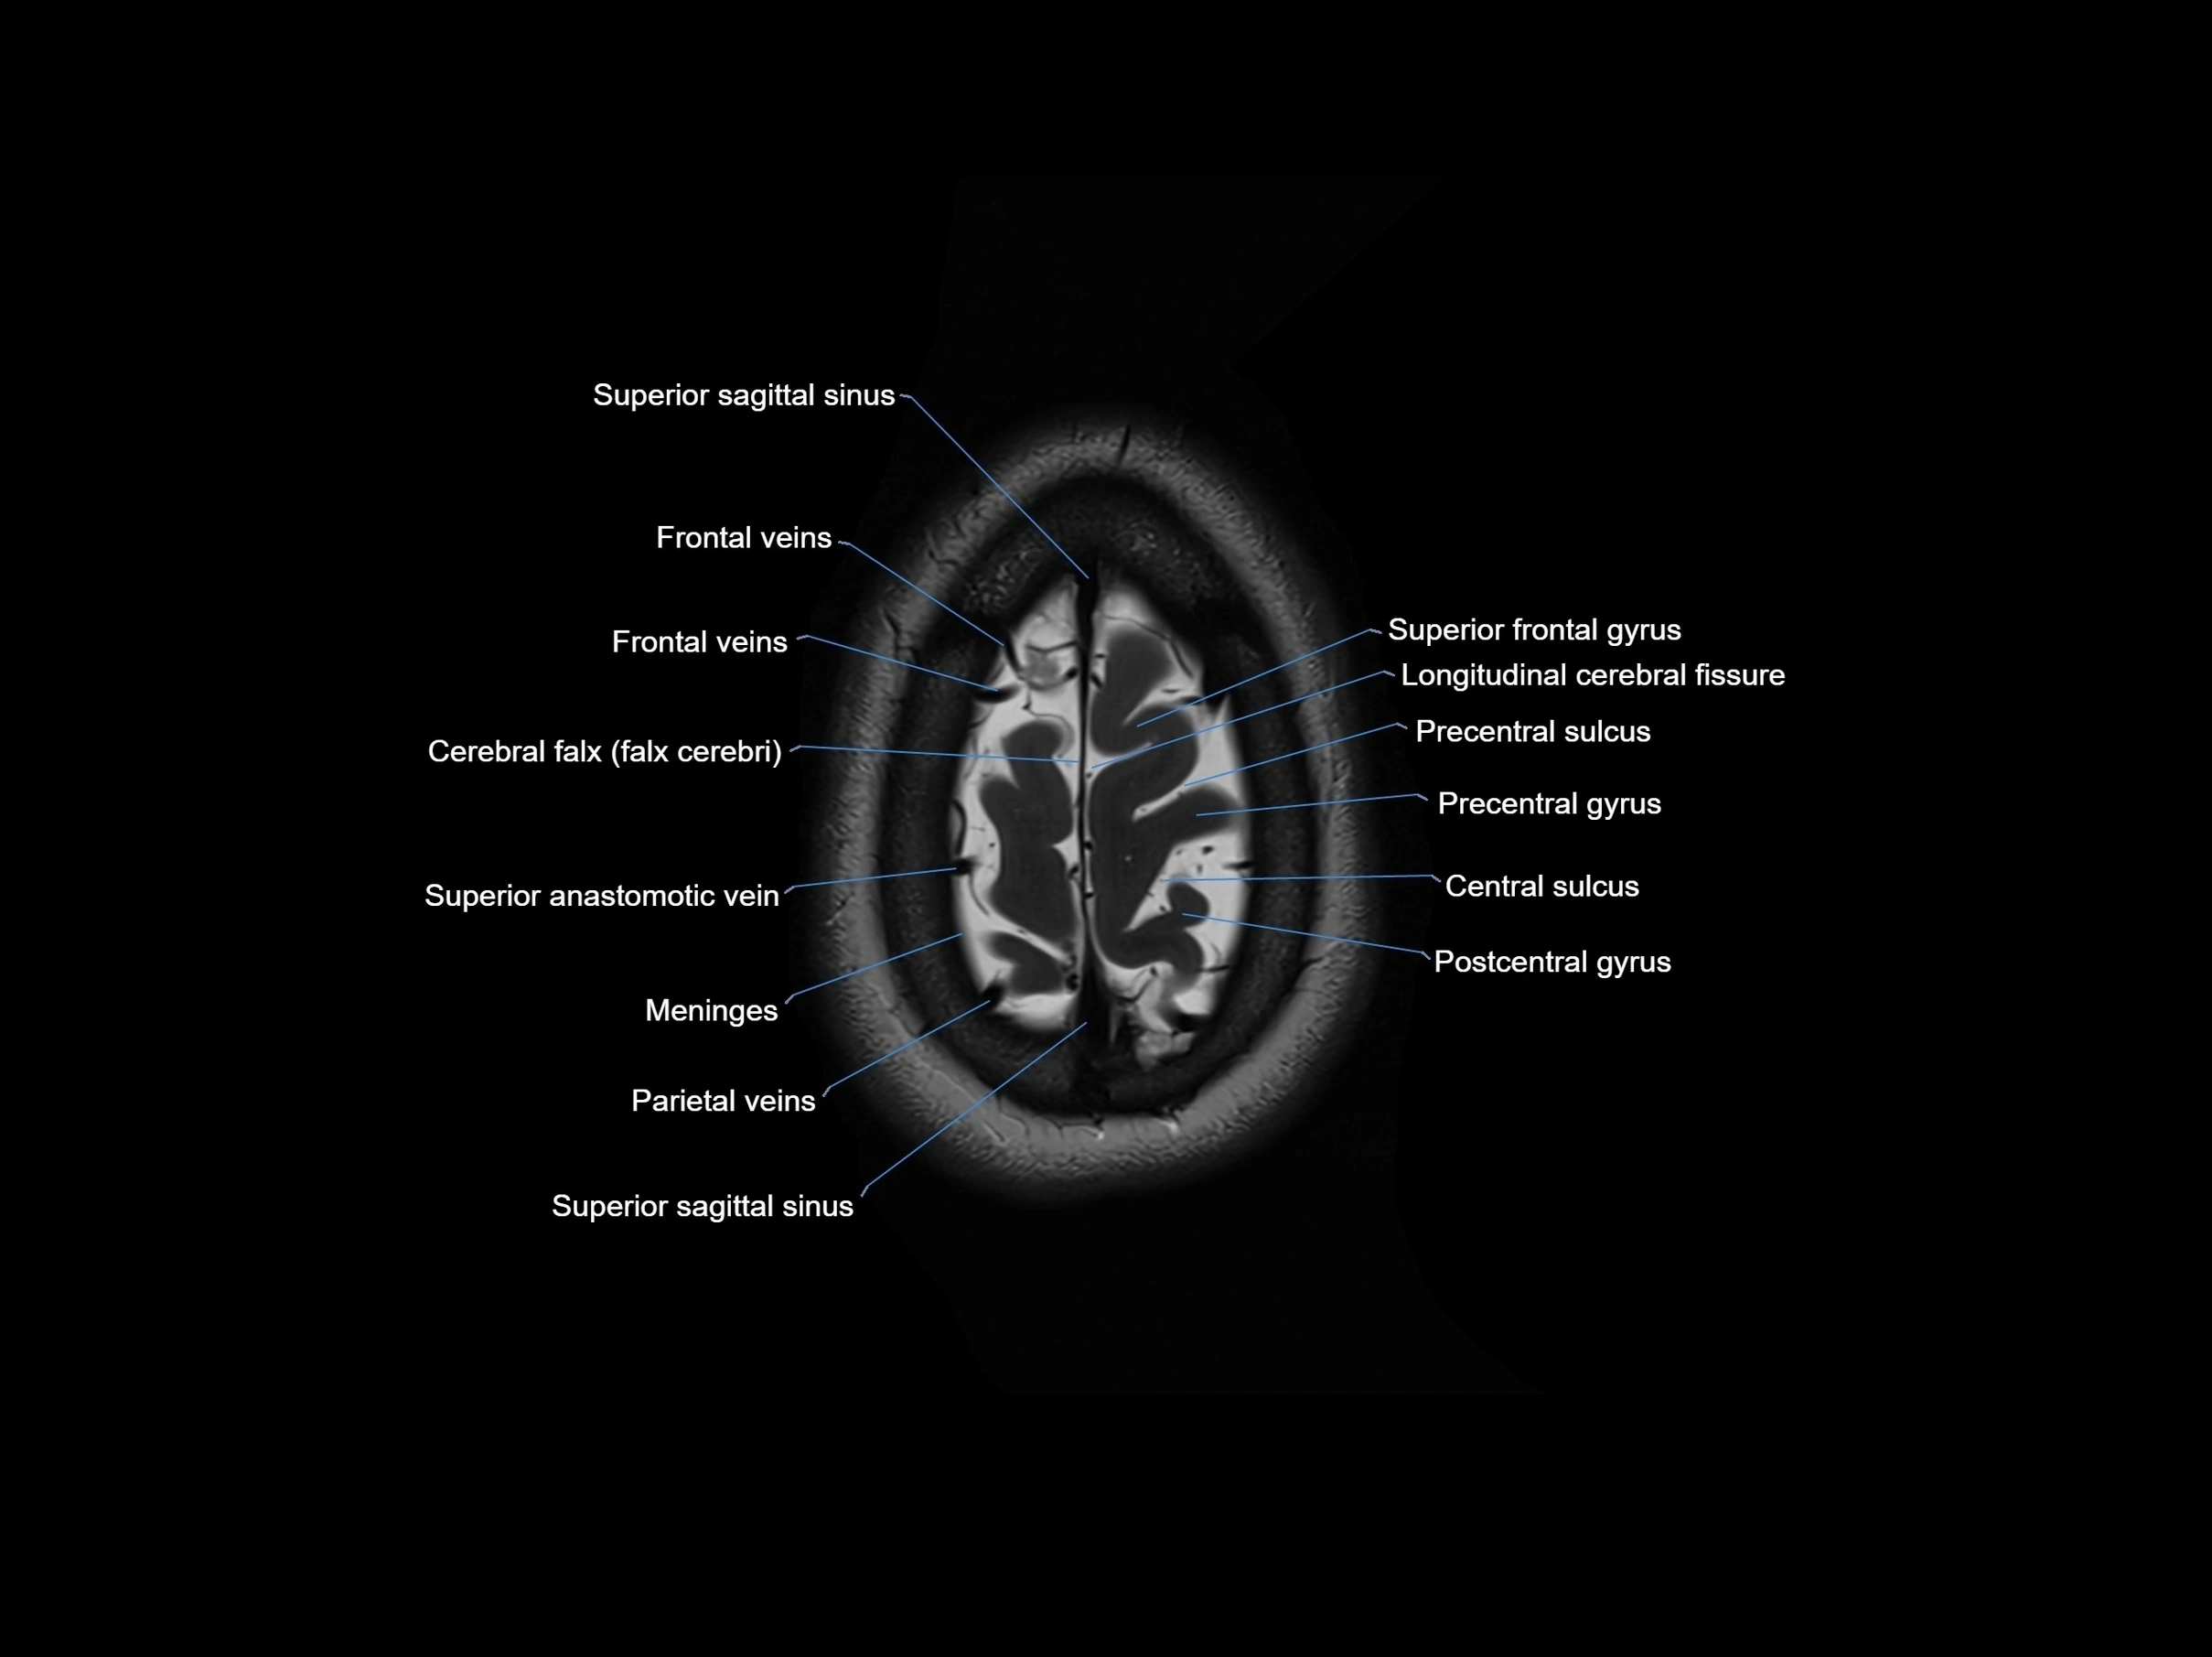

MRI images